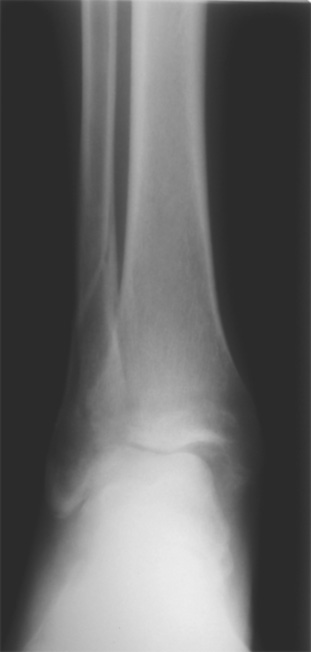

Мне кажется есть все основания попытаться сделать остеосинтез. Боль вследствие нестабильности. Нестабильность вследствие неанатомичного положения дистального отломка малоберцовой кости. Через 1,5 вполне возможно разобщить, репонировать и фиксировать длинный косой перелом наружной лодыжки. Вероятно, одновременно придется делать медиальный доступ для мобилизации внутренней лодыжки. Мы оперируем таких пациентов, функциональные (объем движений) результаты конечно хуже по сравнению с теми кого оперируем в первые 5-10 дней, но вполне удовлетворительные.

Согласен, на предоставленных рентгенограммах все основания для проведения открытого остеосинтеза.

сроки действительно небольшие, но если мы его и возьмем, то пройдет еще минимум неделя, кроме того смущает впечатление сращения н/лодыжки, похоже, что придется не разобщать,а остеотомировать, формирование оссификатов в полости сустава с медиальной стороны, да и сам пациент 1,5 месяца по поводу своей травмы сильно не напрягался

Здравствуйте.На мой взгляд, нужно попытаться сделать остеосинтез внутренней лодыжки. Самое главное-как устранить подвывих стопы кнаружи.Начинать все равно нужно с МОС наружной лодыжки (не исключена и остеотомия на уровне сустава).Если достигнется медиализация стопы-приступайте к МОС внутренней лодыжки.После удаления рубцовых тканей даже не думайте о маллеолярных винтах(постиммобилизационный остеопороз, проверено)-2 спицы и проволка(по Веберу).Что касается артродеза - рано, гипс-глупо.Каждый день уже не в Вашу пользу

Здравствуйте, Максим! Мое мнение - оперировать, вот только срок после травмы определяет последовательность оперативных действий. В свежем случае при таком повреждении операция начинается с репозиции и синтеза наружной лодыжки, затем - вмешательство на внутренней стороне. В данном случае ригидность тканей может не позволить Вам, начав операцию снаружи, произвести адекватную репозицию. Мы в таких случаях поступаем следующим образом: начинаем с внутреннего доступа, из которого производим мобилизацию внутренней лодыжки. Затем из наружного доступа выполняем мобилизацию перелома наружной лодыжки. После этого достигается мобильность, характерная для свежего перелома. Синтез производим в последовательности: наружная сторона, синдесмоз (при необходимости), внутренняя сторона. 6 недель - не критический срок. Удавалось восстановить повреждения 3-4 месячной давности с хорошими функциональными результатами. А почему больных с такими сроками после травмы очень много - совсем другой вопрос. Кстати, почти наверняка сращения еще нет. Удачи! Константин Деданов, Челябинск, Областная больница